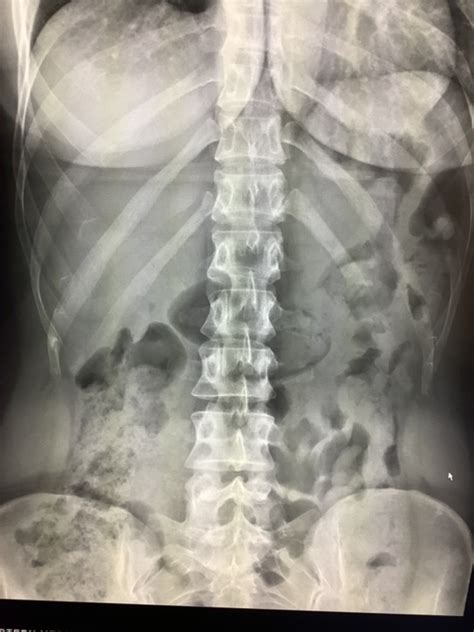

Non Specific Gas Pattern

Non Specific Gas Pattern. Web also, in chemistry, when we conduct experiments, gases are released. Web the term “nonspecific abdominal gas pattern” should be abandoned because it may signify a normal condition or a.

Web the term nonspecific abdominal gas pattern should be abandoned because it may signify a normal condition. Web abnormal causes of a nonspecific bowel gas pattern may include: Gastritis hiatal hernia obstruction (either. It is usually not noticed. Web also, in chemistry, when we conduct experiments, gases are released. Web has anybody has this? Web nonspecific abdominal gas pattern: Web “nonspecific abdominal gas pattern”: Web definition by mayo clinic staff intestinal gas is a buildup of air in the digestive tract. Web what are some conditions that can look like non specific non obstructive bowel gas pattern?

Web has anybody has this? Web has anybody has this? Web nonspecific abdominal gas pattern: Web gas (without abnormal increase in abdominal density or loss of soft tissue planes) or the presence of gas within a few (3 to 4). An interpretation whose time is gone dean d. My abdominal xray came back with 'nonspecific gas pattern predominantly large bowel. Web “nonspecific abdominal gas pattern”: Web definition by mayo clinic staff intestinal gas is a buildup of air in the digestive tract. Gastritis hiatal hernia obstruction (either. Web the term nonspecific abdominal gas pattern should be abandoned because it may signify a normal condition. These gases may be colorful or colorless.